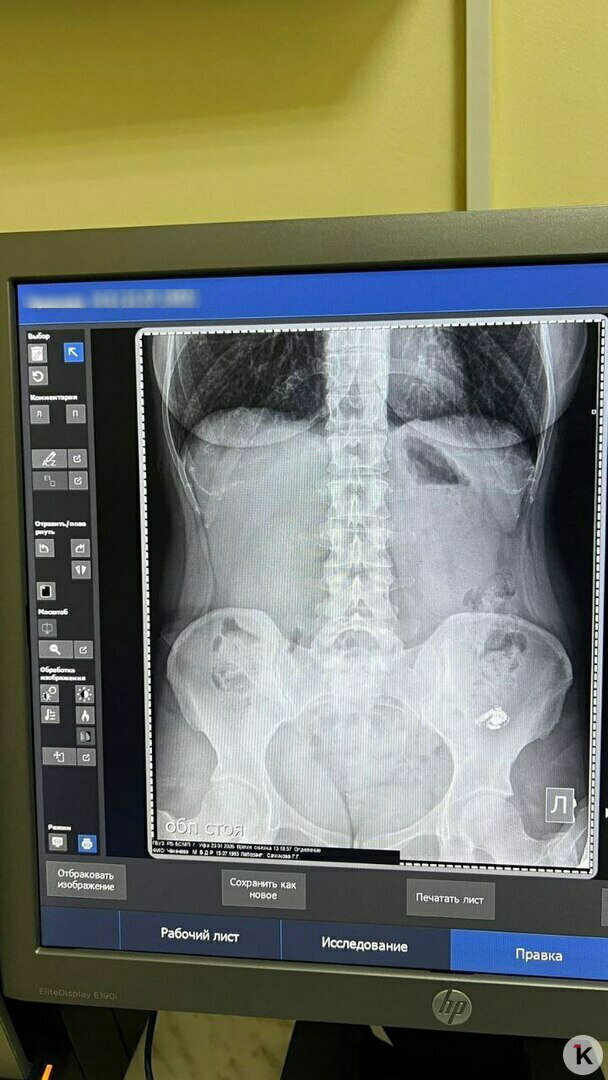

Мария очень испугалась: было непонятно, как поведёт себя внутри организма электронный прибор. Но в травмпункте девушке сделали снимок и обнаружили наушник в желудке. Ей объяснили, что пока ничего страшного не происходит — главное, что он нигде не застрял и не перекрывает дыхательные пути. И порекомендовали подождать, пока гаджет не выйдет естественным путём.

На первом снимке наушник левее: в кадр кроме него случайно попало украшение на теле. Фото: Мария

Повторный снимок, к счастью, подтвердил, что всё идёт как надо, инородный предмет постепенно опускается ниже по ЖКТ. Ей рекомендовали мягкую диету для улучшения перистальтики кишечника и отправили ждать дальше. Наконец, поздно вечером на вторые сутки проблема благополучно разрешилась.